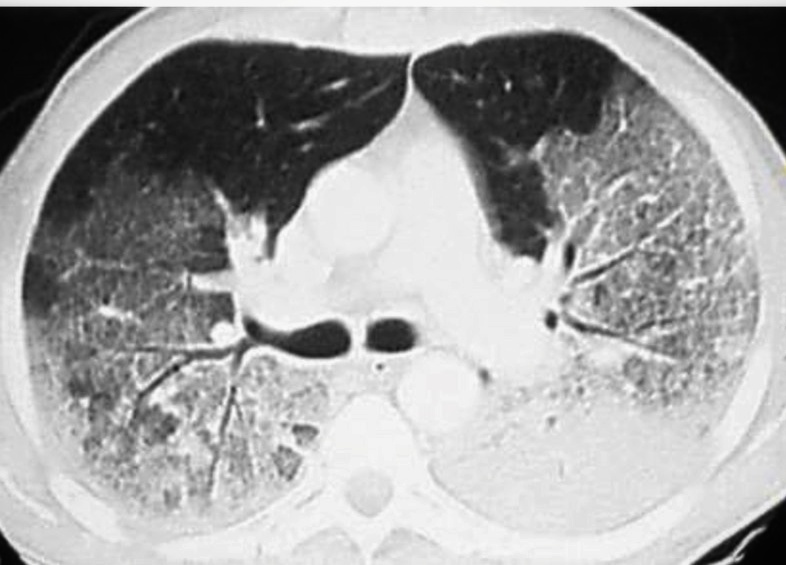

Наиболее опасным осложнением при гриппе является развитие острого респираторного дистресс-синдрома (ОРДС), являющегося крайним вариантом дыхательной недостаточности по типу некардиогенного отека лёгких с выраженным снижением парциального давления кислорода в крови. Состояние жизнеугрожающее, требует лечения в условиях ОРИТ, а на КТ выглядит вот так:

КТ ОГК на уровне бифуркации трахеи, аксиальный срез: пневматизация лёгочной ткани выраженно снижена за счёт диффузно расположенных участков "матового стекла" и консолидации, преимущественно локализующихся в дорсальных и базальных отделах лёгких (эффект градиента).